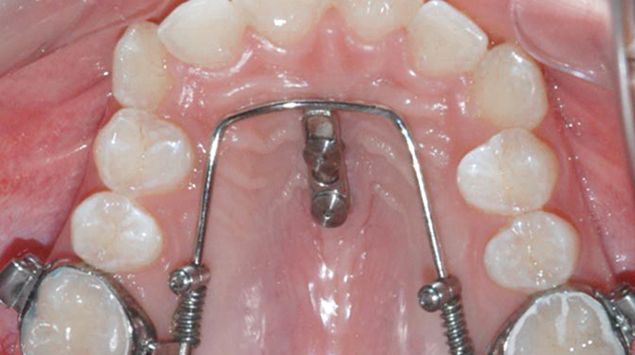

>   Beneslider na podniebieniu.

Beneslider to aparat ortodontyczny przeznaczony do przemieszczania zębów wzdłuż łuku zębowego. Dzięki kostnemu umocowaniu, Beneslider umożliwia przesuwanie zębów bez konieczności zaangażowania pacjenta, co pozwala uniknąć ekstrakcji zębów.

Elementy aparatu Beneslider:

2 mikroimplanty,

Metalowy stelaż (tzw. Beneplate),

Sprężyny nitinolowe,

Aktywatory,

Tuby dołączone do pierścieni.